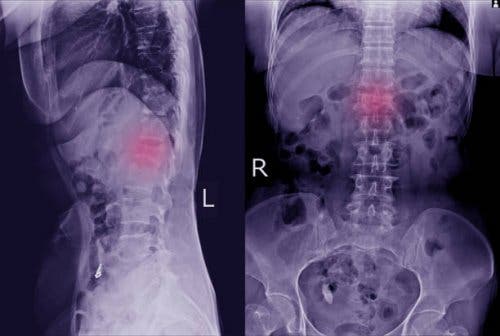

Deze fysieke manifestaties zijn gemakkelijk over het hoofd te zien. Als je er echter op let, kun je naar de dokter gaan om een van de belangrijkste tests uit te voeren waarmee ze kunnen worden gedetecteerd. We hebben het over röntgenfoto’s. Op die manier is het mogelijk om duidelijk te zien of er sprake is van een verplaatste wervel.

In sommige gevallen kan de arts meer specifieke tests nodig hebben, zoals een computertomografie of een MRI-scan. Met deze aanvullende tests kunnen ze duidelijker zien of er sprake is van spondylolisthesis en ook of het botten en zenuwen heeft aangetast.